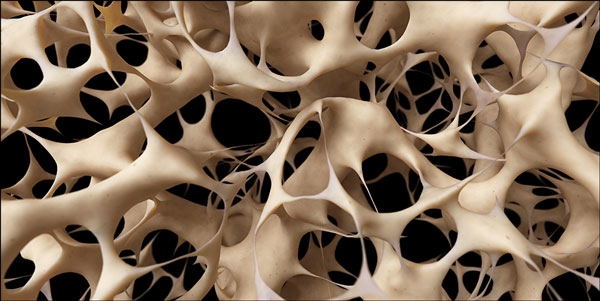

هشاشة العظام، والمعروفة أيضاً باسم ترقُّق العظام، هي حالة تضعف فيها العظام وتصبح أكثر عرضة للكسور، وتُعدُّ هذه الحالة من أكثر أمراض العظام شيوعاً، خاصةً عند النساء بعد سن اليأس.

تحدُث هشاشة العظام عندما يخسر الجسم من كثافة العظام، ويكون سبب ذلك:

مع تقدُّم العمر، تصبح العظام أرق وأكثر عرضة للكسر.

1. زيادة كثافة العظام:

أظهرت الدراسات أنَّ شرب الحليب قد يساعد على زيادة كثافة العظام وتقليل خطر الإصابة بالكسور.